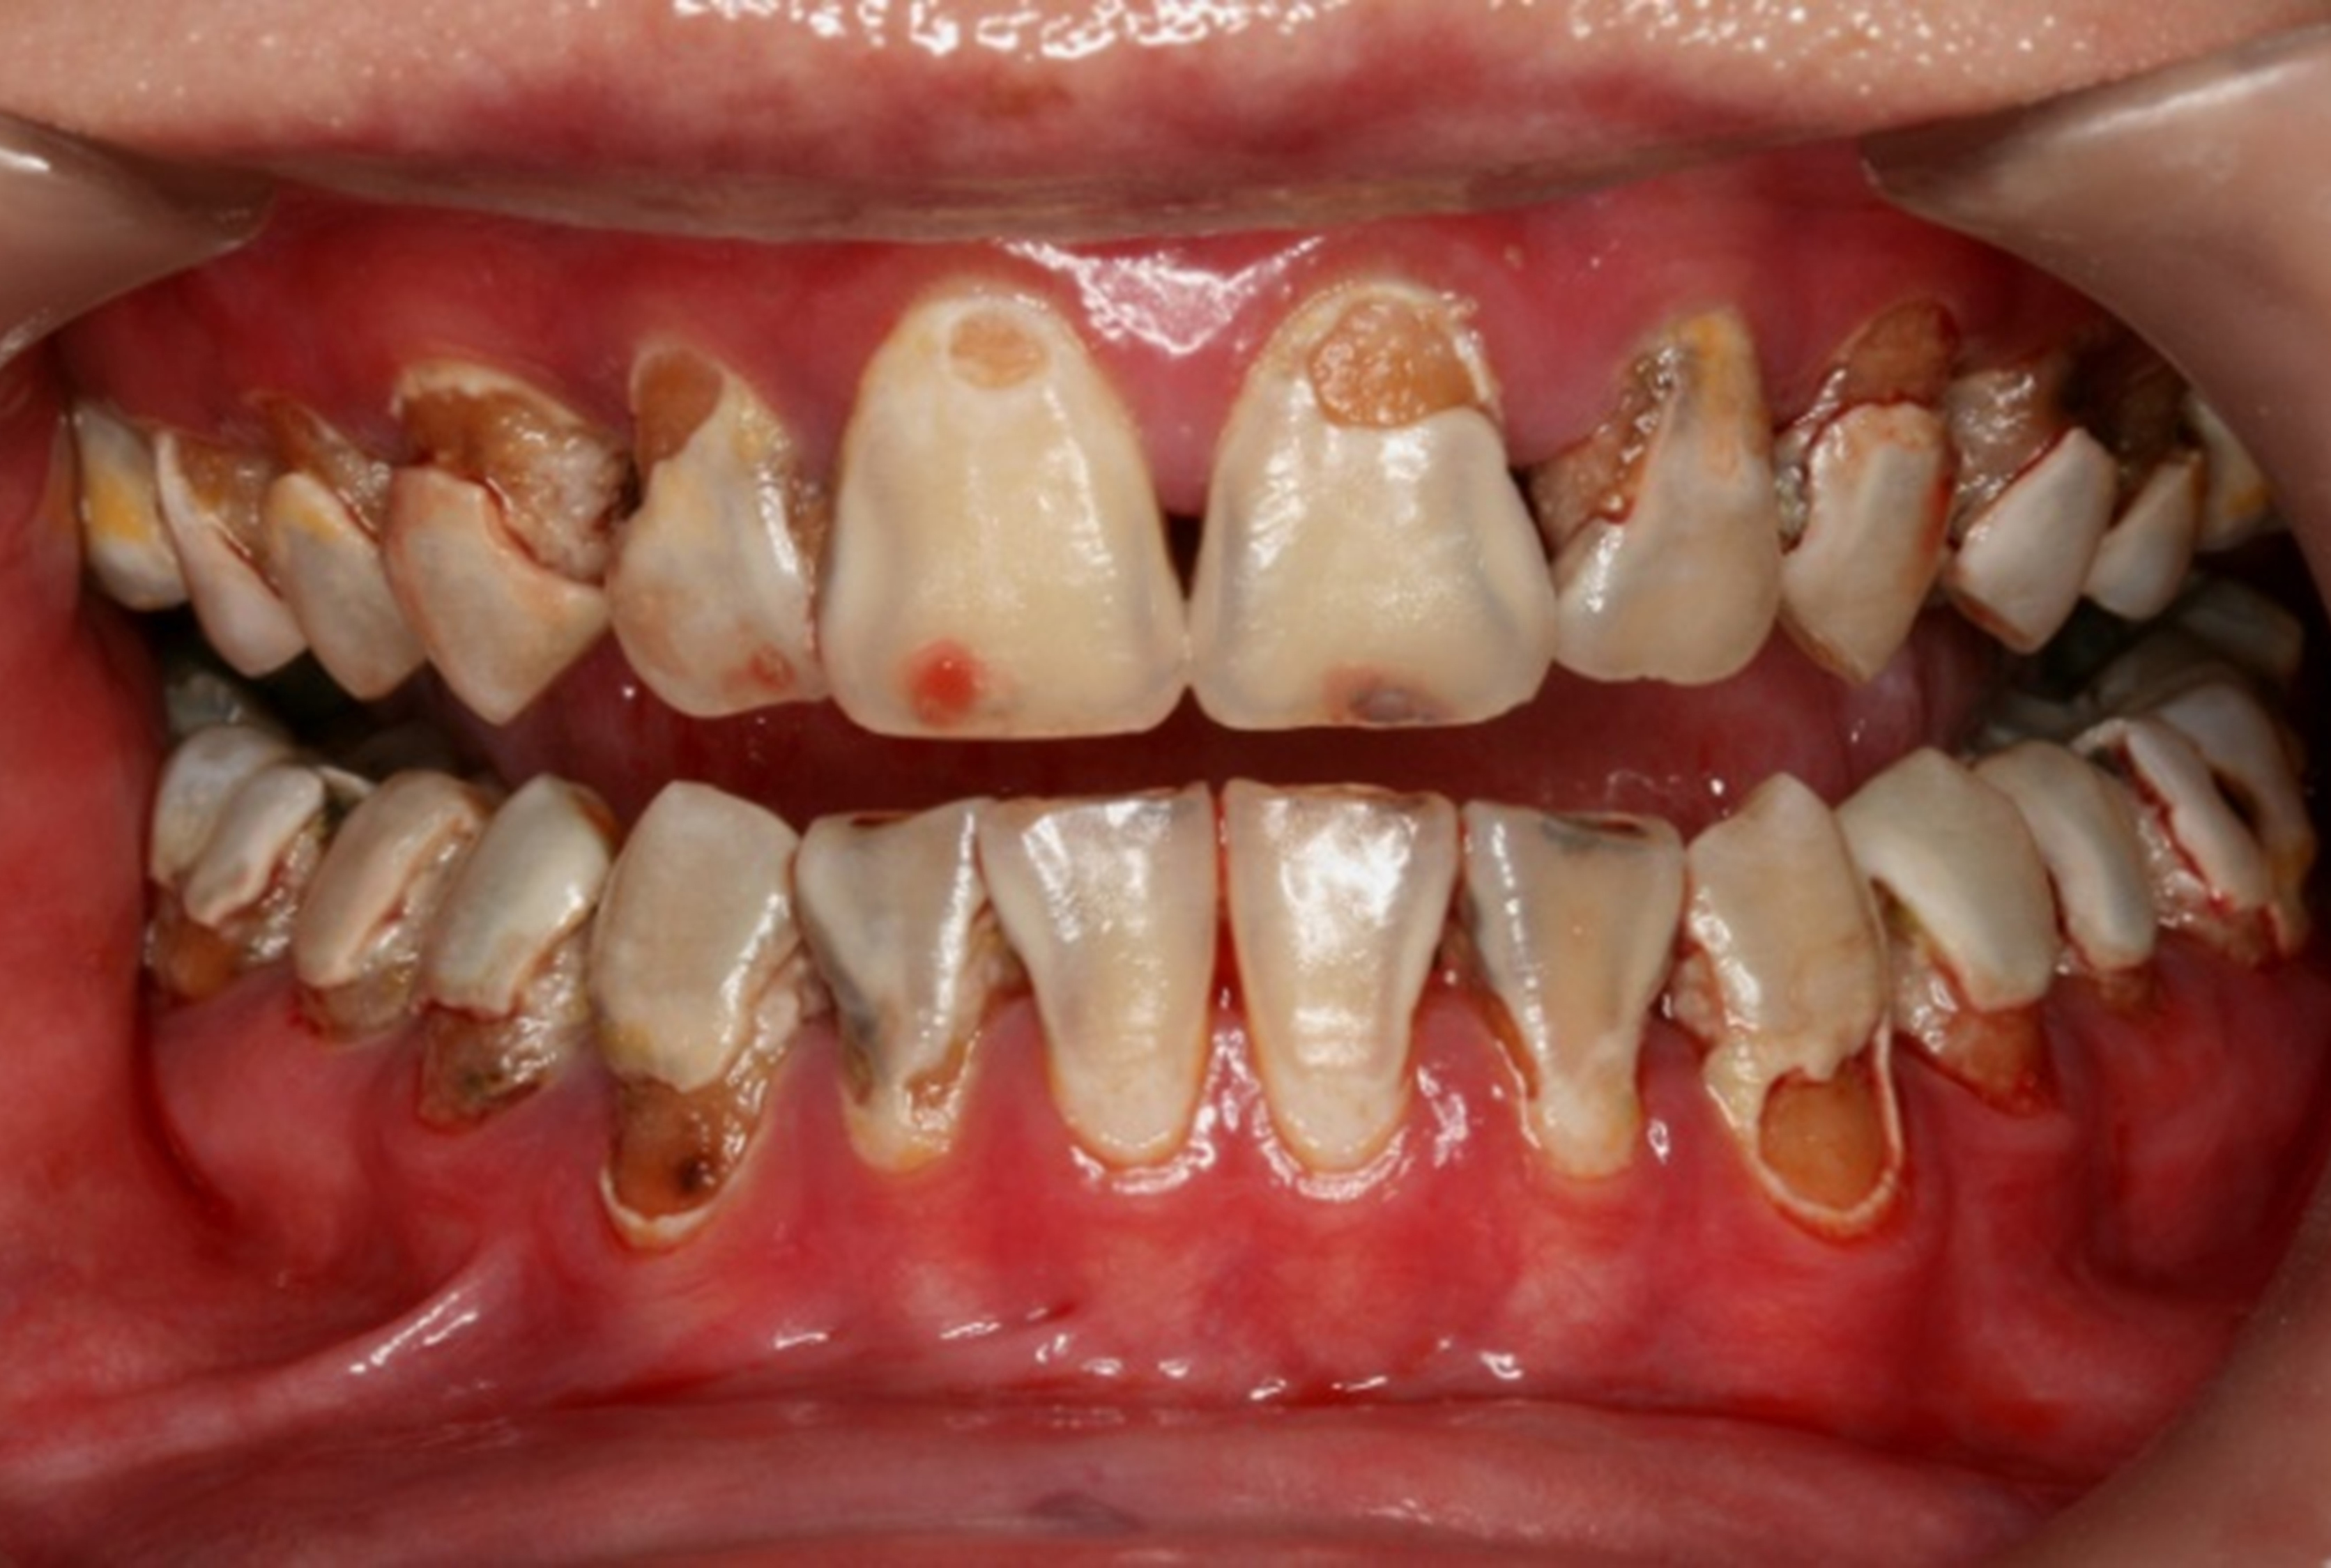

Fig 8. Use of 38% SDF to arrest rampant caries in a young teenager: pre-treatment intraoral frontal view of rampant caries. (image from Chu, et al, 2014, ref 36 [reprinted with approval])

Figure 8

The inherent disadvantage of SDF is that the caries lesions will be stained black after SDF application. SDF stops caries progression by forming a hard, blackened, impermeable layer on the tooth surface that is resistant to caries (Figure 5 through Figure 9). The authors’ clinical observations are that the darker the color, the more likely the caries arrested. Some patients may not be pleased with the esthetics of this treatment outcome; therefore, it is important to inform the patients and parents (for child patients) about this treatment outcome. Moreover, SDF can stain clothes and the skin of the body. Though it does not cause any pain or damage, an SDF stain on skin cannot be easily washed away. It takes around 7 days for it to disappear, and the stain on clothes is permanent.22

There is no consensus on the frequency of application, and 38% SDF has been used annually or biannually on clinical trials in children23,31,33,34 and in elderly.30,35 Yee and his co-worker found one-off application of 12% SDF was ineffective in arresting caries in children.31 The present authors applied 38% SDF weekly for 3 weeks to speed up the process of caries arrest and for treatment of rampant caries.36 One of the present authors’ case reports demonstrated that three weekly applications of 38% SDF can arrest rampant caries and relieve pain from hypersensitivity on a teenager. The SDF-treated caries were found arrested, and they turned coal black in appearance (Figure 9).